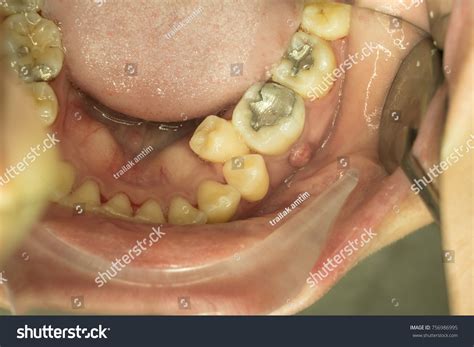

When searching for root abscess pictures, you will often notice a common visual sign: a small, pimple-like bump on the gums near the affected tooth, known as a fistula. While not all abscesses present this way, it is a hallmark sign that the body is trying to drain the infection.

• Gum swelling: The gums near the affected tooth may appear red, swollen, or tender.

• The "Pimple" on the gums: A small, bump on the gums (fistula) that may periodically release a foul-tasting fluid or pus.

• Facial swelling: In advanced cases, the infection can cause swelling in the face, cheek, or neck.